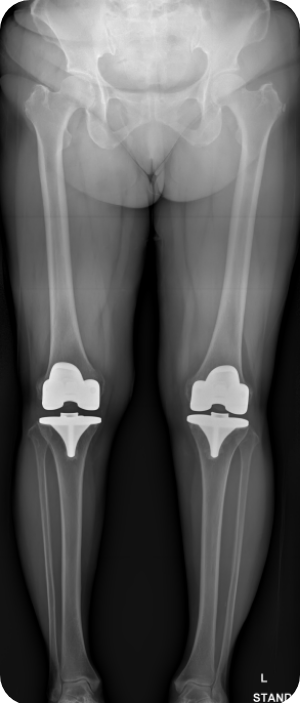

무릎인공관절 전치환술 사례1

• ▲ 수술 전

• ▲ 수술 후

무릎인공관절 전치환술 사례2